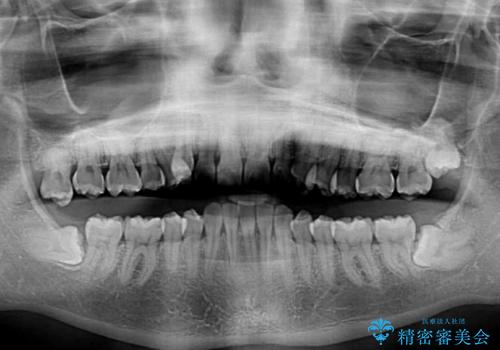

- 八重歯を気にして来院された患者様です。

八重歯の後ろの歯を1歯抜歯し、補助装置(リンガルアーチ)を用いて八重歯の位置を改善し、その後インビザラインにより矯正治療を行うこととしました。

下顎前歯が1本欠損したスリーインサイザーという状態であるため、上下の前歯の咬み込みが深くなったり、奥歯の咬み合わせが理想的なものとならなかったりという仕上がりになってしまいます。

前歯の見た目や奥歯の咬み合わせに、患者様が違和感を感じない状態として治療を終えました。